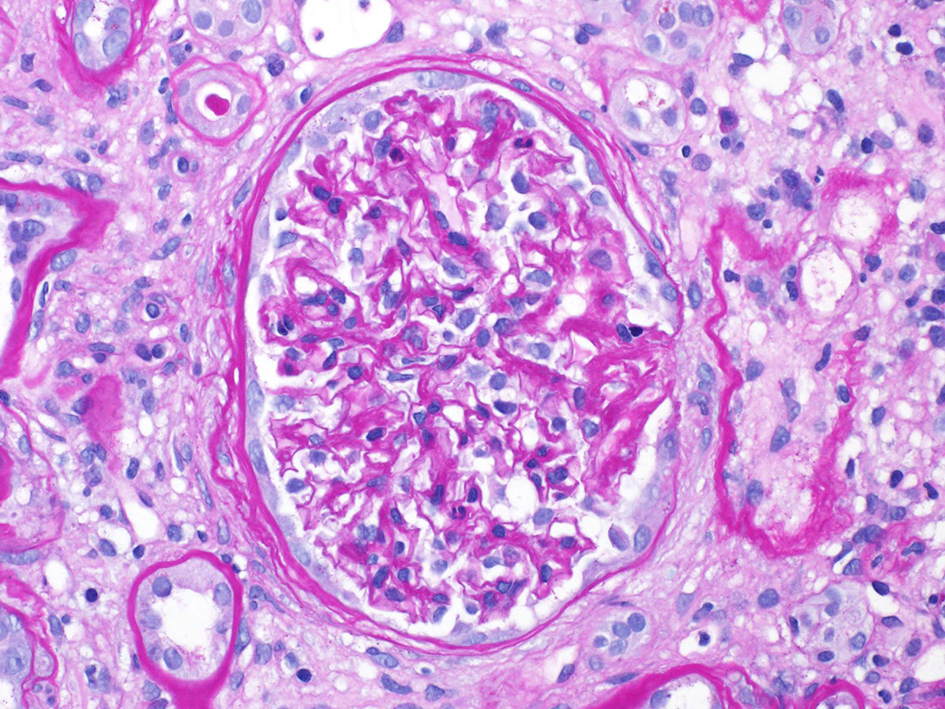

After several days of care and an unremarkable renal ultrasound, a renal biopsy was ordered. The pathology demonstrated 13 out of 23 glomeruli to be globally sclerotic, as well as areas of capillary loop wrinkling and periglomerular fibrosis (Fig. 1). Patchy areas of acute tubular injury were present, with moderate numbers of injured tubules containing luminal calcium oxalate crystals, consistent with oxalate nephropathy (Figs. 2 and 3). Additionally, there was severe interstitial fibrosis and tubular atrophy involving an estimated 60% of the submitted parenchyma, and moderate fibrointimal thickening of small arteries and severe hyalinosis of arterioles (Fig. 4). Immunofluorescence staining for IgG, IgM, IgA, C3, C1q, albumin and fibrinogen were negative, and kappa and lambda light chains stained equally throughout the tubulointerstitium.

![]() Click for large image | Figure 1. Loop wrinkling, periglomerular fibrosis. |